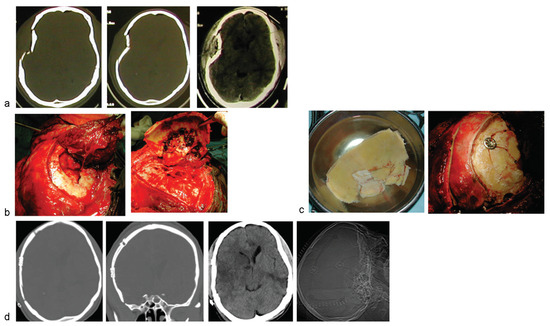

Figure 1.

A young man presented 2 days following moderate head injury sustained out of state; he was referred from another neurosurgery unit. (a) Bone and brain windows of cranial CTshowed comminuted depressed right temporoparietal skull fracture. There were associated brain contusions and cerebral edema, with midline shift. (b) Exposure and elevation of a craniotomy flap incorporating the fracture fragments. (c) Thorough debridement of the fracture site, refixation of the fracture fragments with the 16-mm cranioFix clamp is shown, as well as the operative wound ontable, after closure. (d) Postoperative radiological images showing excellent restoration of the craniofacial symmetry, as well as the titanium implants, low profile, in situ.